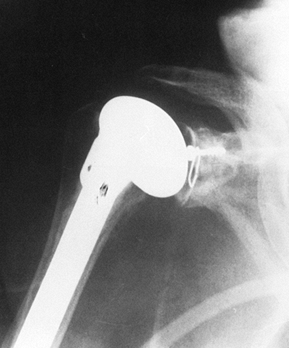

from the severe, unpredictable destruction of both bone and soft

tissue, which is the hallmark of the disease (Fig. 101.51, Fig. 101.52, Fig. 101.53 and Fig. 101.54). Severe medial and superior wear of the

Figure 101.53.

In this patient with rheumatoid arthritis, there is a fracture of the acromion from superior migration, wear into the acromioclavicular joint, and severe medial migration of the humerus with glenoid bone loss. |